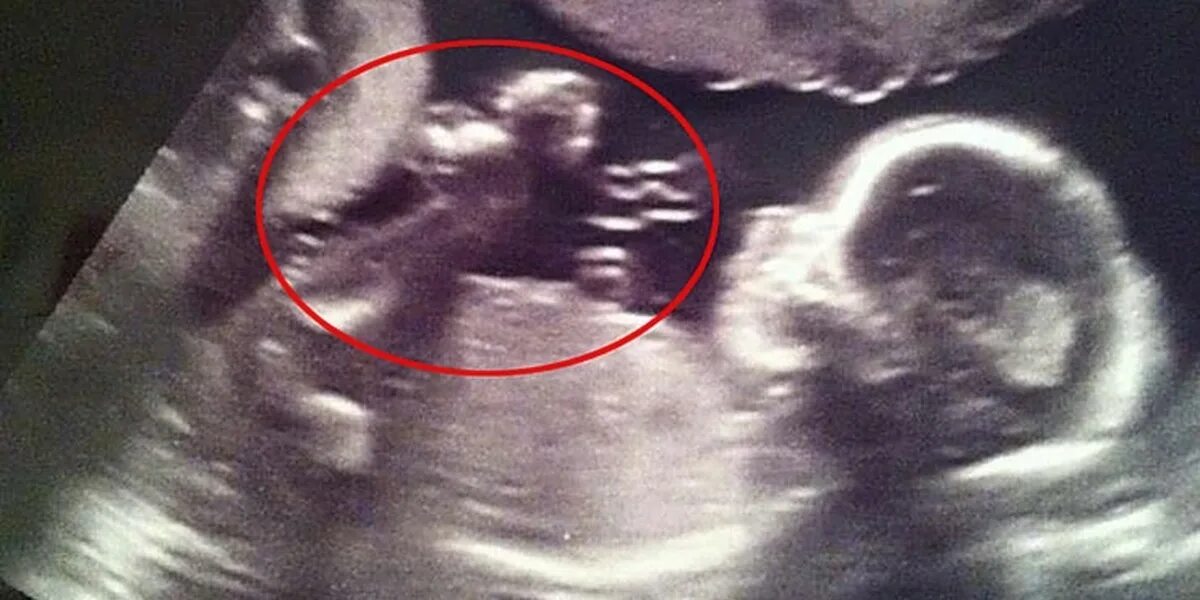

Может врач ошибиться с полом ребенка